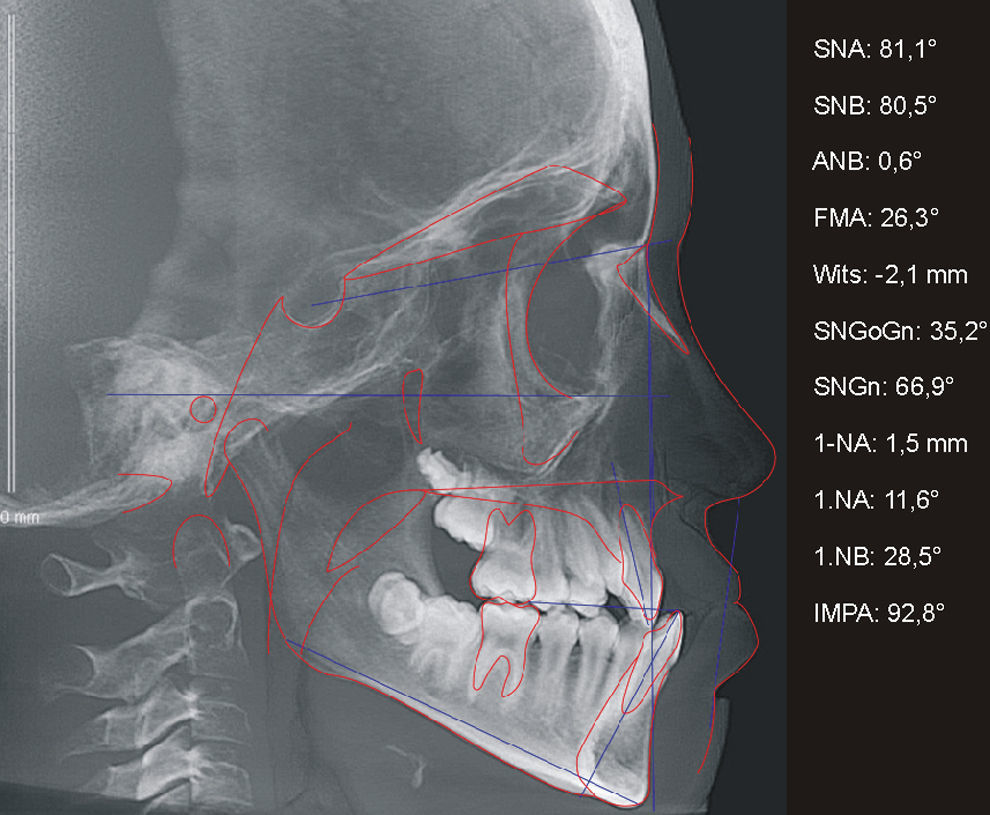

O histórico de cirurgias do paciente B, sexo masculino, se assemelha ao da paciente anteriormente descrito, assim como os efeitos sobre sua maxila e suas características relativas ao perfil facial, padrão esquelético e dentário (figs. 5 e 6). Igualmente acompanhado pelo CENTRARE, concordou‐se em iniciar a ERM aos 12 anos. Realizados exames clínicos e TCFC, observou‐se: tendência a uma má oclusão esquelética de Classe III (ANB=0,6°; Wits=–2,1mm), maxila bem posicionada em relação à base do crânio (SNA=81,1°), incisivos superiores retroposicionados e retroinclinados (1.NA=‐1,5mm; 1.NA=11,6°) e incisivos inferiores bem posicionados na base óssea (1.NB=28,5 graus; IMPA=92,8 graus) (fig. 7). Diante da necessidade de expansão limitada à região anterior, foi instalado em JFRL o disjuntor mini‐Hyrax invertido com BTP11. Confeccionado com um mini parafuso (Variety Expander, DynaFlex, Saint Ann, Missouri, EUA) posicionado na região mais anterior possível do palato. Extensões provenientes do parafuso (fio 1,4mm) contornaram a superfície palatina dos caninos, passando pelas bandas nos primeiros pré‐molares e chegando até à superfície palatina dos segundos pré‐molares. Além disso, uma BTP (fio 0,9mm) foi soldada em bandas nos primeiros molares permanentes (fig. 8).